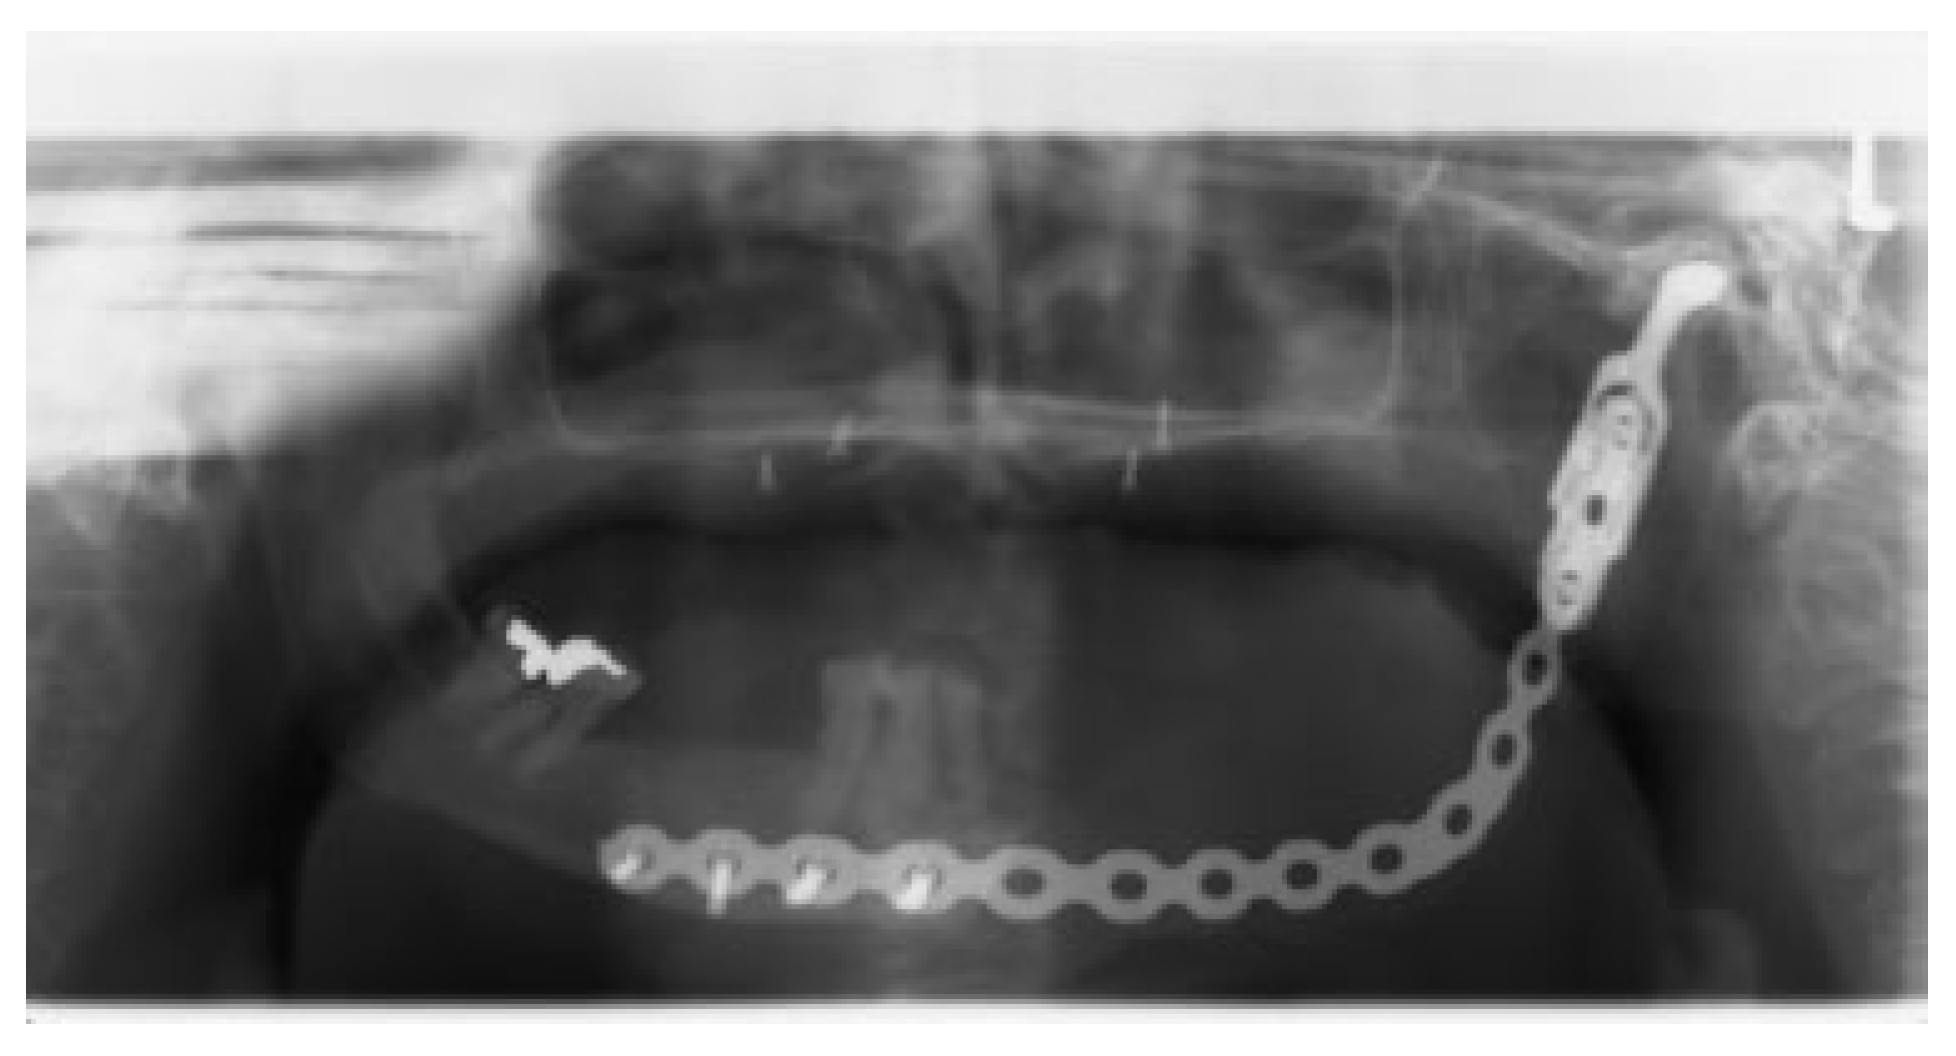

In 15 patients, 14 ablative surgical interventions were recorded, with 14 receiving primary or secondary reconstructive procedures; in one patient, no reconstructive procedure was performed due to a compounding medical condition (Table 2). This patient was excluded from further analysis due to lack of reconstruction. Eight patients had primary head and neck cancer, but in only four patients the condyle was involved due to infiltration, while four suffered from ORN. One patient suffered from a rare benign tenosynovial giant cell tumor. Two patients suffered from extensive osteomyelitis, and bisphosphonate osteonecrosis afflicted two patients. One patient had to be operated on twice due to hypertrophic bone formation around the metal condylar head and represents the only major complication in our series. She suffered facial nerve damage during the second surgery in a postradiated field, with the facial nerve lying on the reconstruction plate used in the first surgery (Figure 1). Six of the fourteen reconstruction surgeries took place in a radiated field, explaining the two plate exposures in an unrelated area, away from the condylar reconstruction. Two patients received total joint reconstructions combined with one and in the other two free flaps. Five patients received fibula flaps alone and one received a vascularized costochondral graft, while all of the others had metal condylar prostheses with or without a free flap (Figure 2, Figure 3 and Figure 4). Follow-up ranged from 2 to 84 months with an average of 30 months. In total, five patients suffered from complications that could be considered acceptable, as they all could be corrected with minor revision surgery or occlusal adjustment. One patient suffered from facial nerve damage after a reconstruction plate in which metal condyle had to be removed in a radiate. In 11 patients, reliable information was obtained regarding mouth opening of which 9 showed a marked improvement of more than 5 mm. Three patients had a decrease in mouth opening, but all could be regarded as functional as no mouth opening of less than 30 mm was recorded (Figure 4).

Figure 3.

Composite fibula free vascularized flap in place.